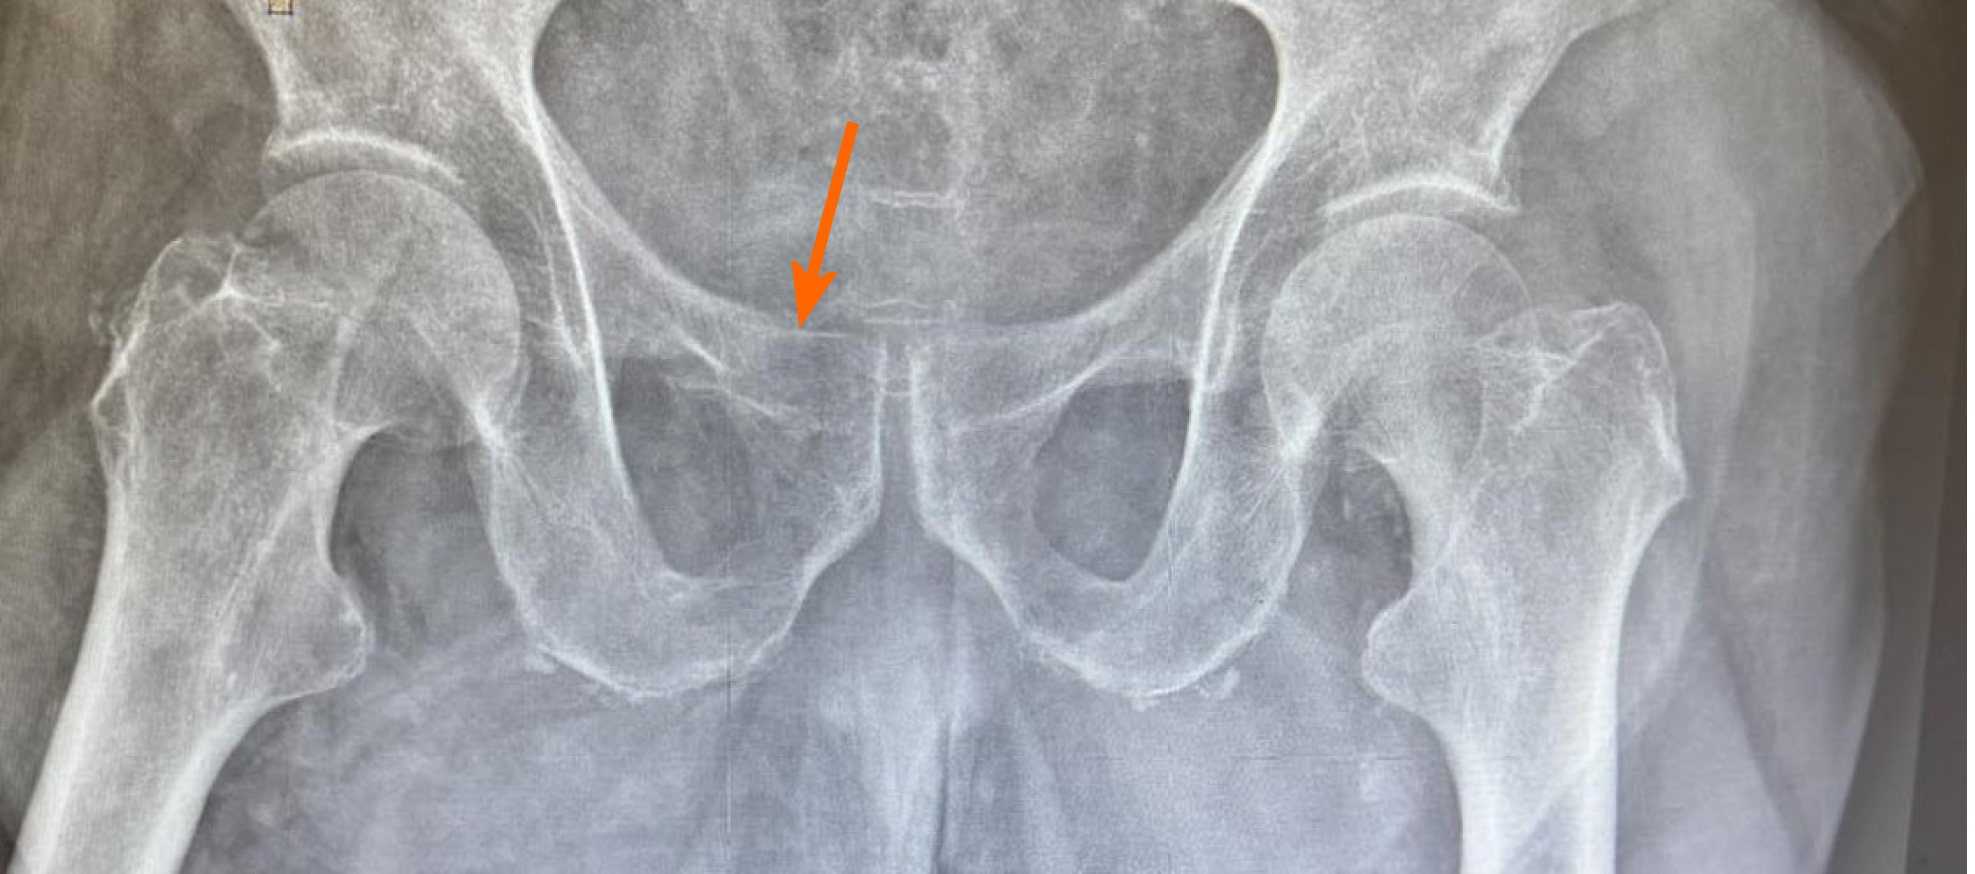

A plain pelvis X-ray was carried out, demonstrating an isolated right superior pubic ramus fracture (Figure 1). Forthwith after the initial diagnosis of the injury, a pelvis computed tomography (CT) scan was conducted for more rigorous evaluation of the fracture (Figure 2). No considerable hematoma was observed at this CT scan.

Isolated right superior pubic ramus fracture.